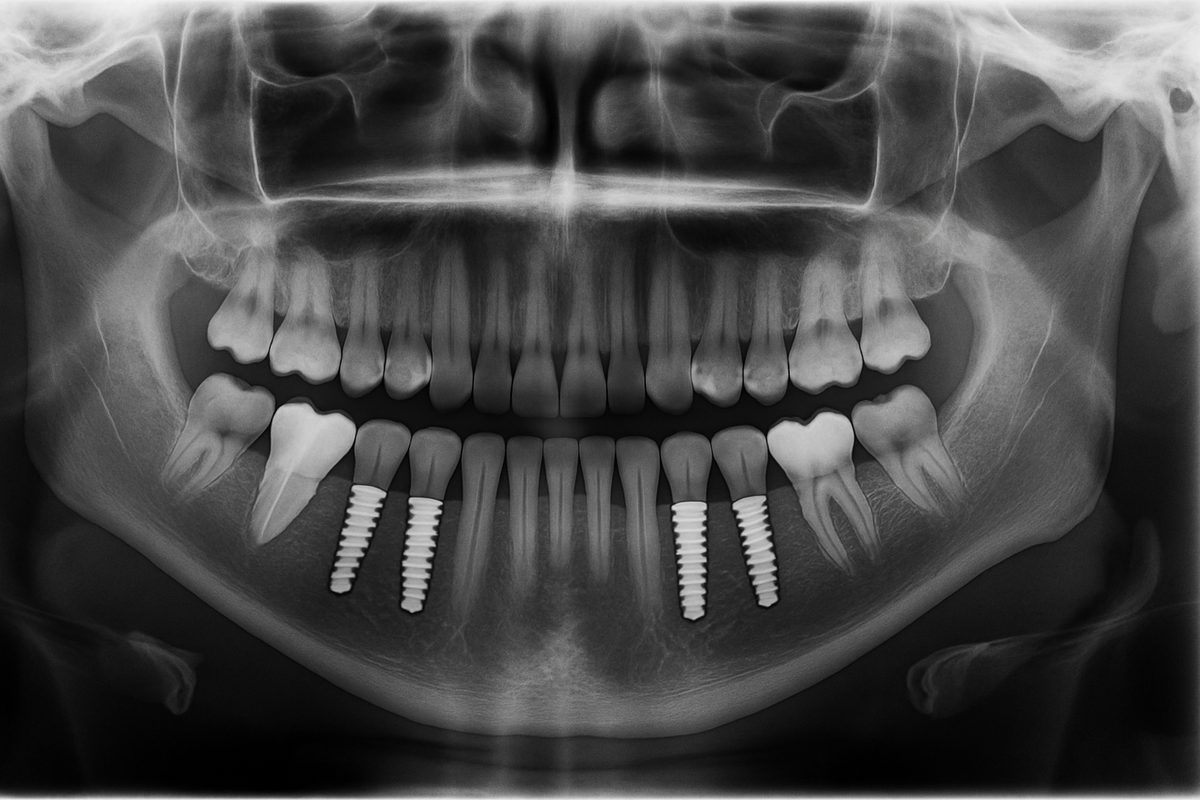

Implant teeth are metal posts surgically placed into the jawbone to act like natural tooth roots. After the bone fuses to the post, a crown, bridge, or denture is attached. Unlike traditional dentures or bridges, implant teeth preserve bone and do not rely on neighboring teeth for support.

Full-arch solutions (All-on-4 / full-mouth reconstructions) restore an entire upper or lower set of teeth with a fixed prosthesis anchored on four or more implants. Many patients can get a same- or next-day smile with immediate-load protocols.

A consultation includes exams, digital scans, and CBCT 3D imaging to map bone and nerves. Planning ensures precise implant placement for implant teeth in The Villages, FL.